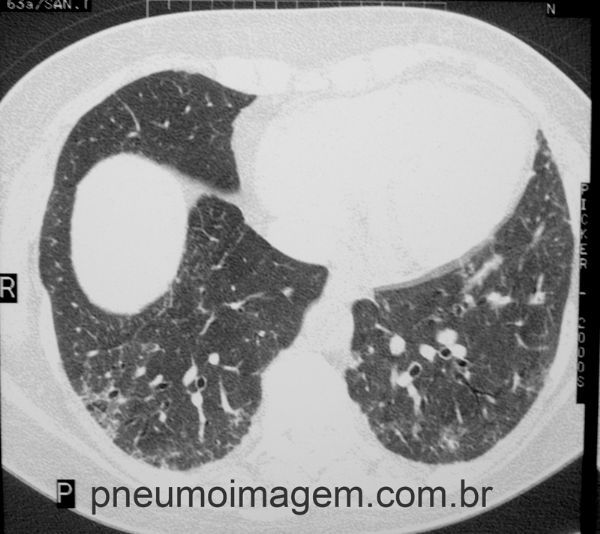

Detalhe de corte tomográfico com distorção da arquitetura pulmonar com bronquiectasias de tração.

Detail showing distortion of pulmonary architecture with traction bronchiectasis.

Alterações intersticiais pulmonares bilaterais difusas e com predomínio nas regiões subpleurais dos lobos inferiores, caracterizadas por espessamento septal interlobular, reticulado, bronquiolectasias de tração, bronquiectasias de tração e faveolamento. Esse é o padrão de pneumonia intersticial usual (PIU), característica da Fibrose Pulmonar idiopática (FPI).

Diffuse biliary interstitial changes with predominance in the subpleural regions of the lower lobes, characterized by interlobular septal thickening, traction bronchiolectasis, traction bronchiectasis and honeycombing. This is the pattern of usual interstitial pneumonia (UIP), characteristic of idiopathic pulmonary fibrosis (IPF).